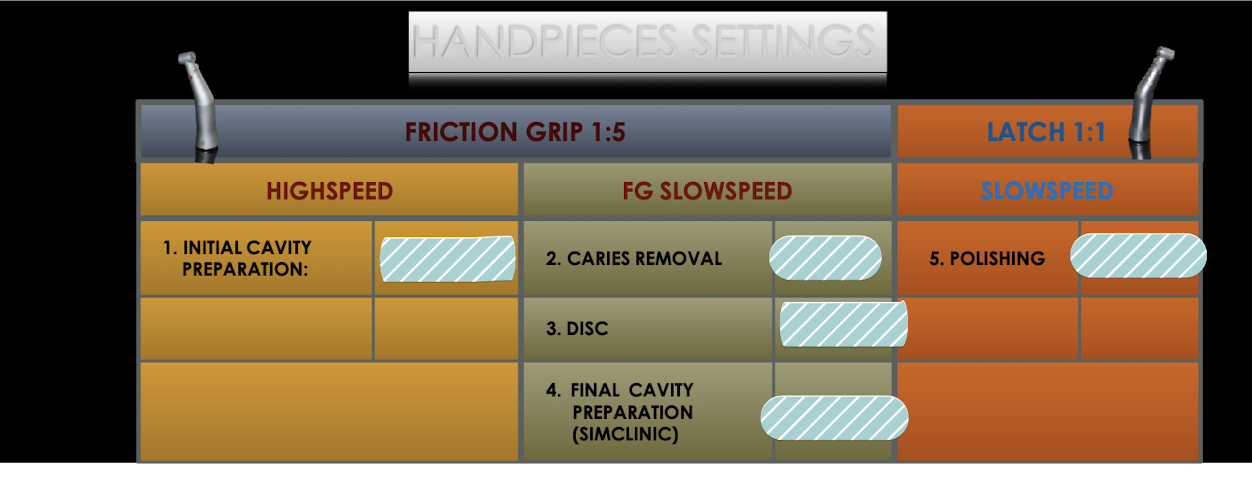

Gen principles of class V glass ionomer preps

All friable/weakened (unsupported) enamel should be ?

Do not extend to ?

When possible, preserve structure beyond ?

__ curves, no ?

Pulpal depth __ bulk for strength (__ mm from DEJ)

__ degrees cavosurface margin (no _)

bur should always be __ to surface you are cutting, and _ to enamel rods

Class V black’s prep:

__ shape

Class V - Blacks Prep

Internal Form

All external walls are __ to the external tooth structure, thereby _ the enamel rods

Extend the prep incisally, gingivally, mesially, and distally until all external walls are positioned in sound tooth structure at pulpal depths ranging from ___ mm at gingival wall to __ mm at incisal/occlusal wall

Axial wall

Depth of __ inside the DEJ

Follows the contour of the ?

__ mesio-distally, leaves dentin bulk for ?

Roughly __ to external tooth surface occluso-gingivally

orientation of walls

All four walls must meet the cavosurface at __ degrees

All walls will __ from axial wall to the cavosurface

Class V basics: outline form (sim lab) vs clinic

Extend to line angles, clinical extend to only enough to remove caries + unsupported enamel

class V GI prep:

Establish outline form:

Use a #____ or #___ bur for initial access and to develop __ internal line angles

Use a __L carbide bur to develop _ prep of walls

Extend to mesial and distal __ __

___, flowing __ (kidney bean shape)

Positioned __ mm supragingival, _ incisal/occlusal-gingival height (dependent on tooth)

Establish __ axial wall

Axial depth at ___ mm incisally/occlusally and __ mm gingival